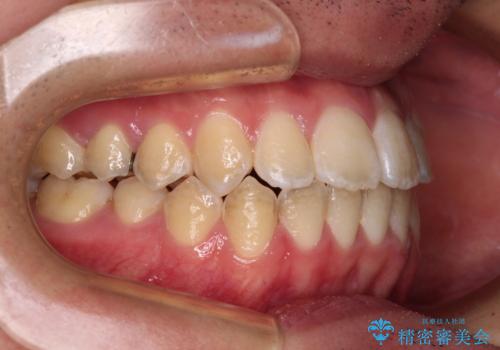

- 上下前歯のデコボコを気にして来院された患者様です。

ワイヤー矯正でもマウスピース矯正でも可能でしたが、短期間で、自身の手を煩わせることなく治療を行いたいとのことで、ワイヤー装置にて矯正治療を行うこととしました。

当初予定通り、1年間で治療を終えることができました。